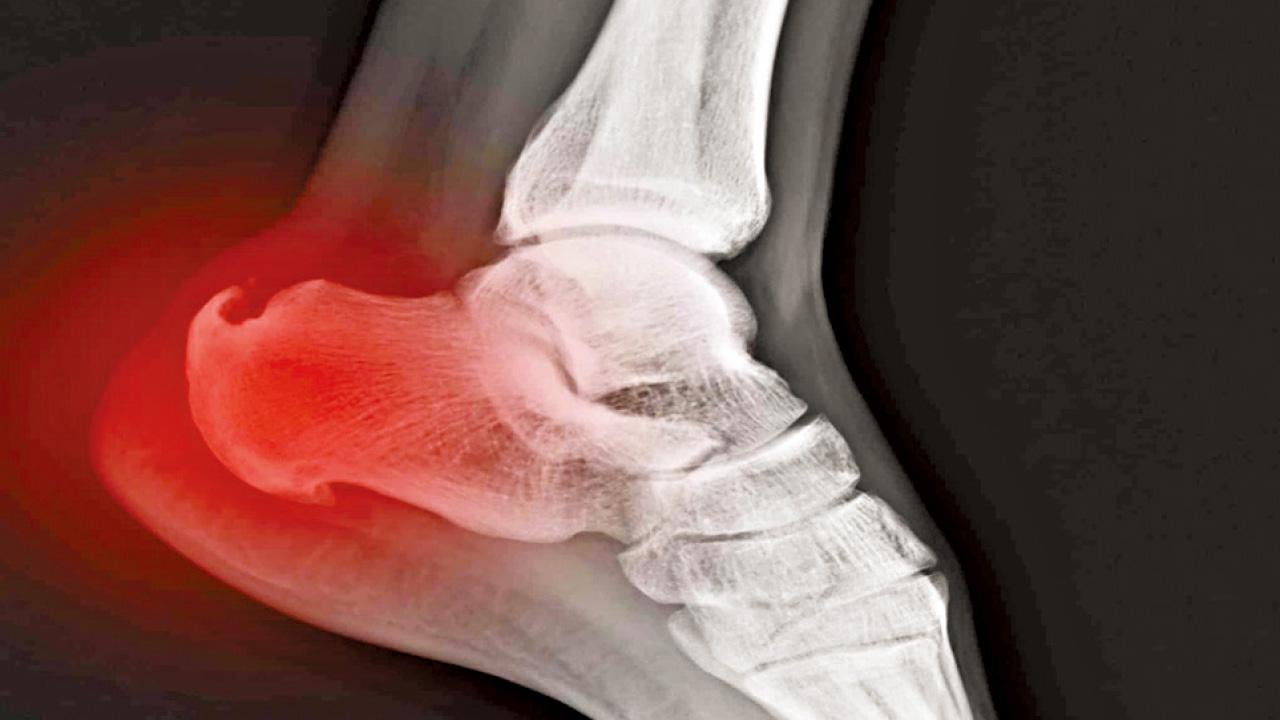

用手摸一摸自己頸椎後側,如果觸感冰涼僵硬,轉頭時會有微微的刺痛感,那就很可能已經罹患頸椎病。這種病變部位僅停留於頸部肌群、韌帶和關節囊軟組織的急性損傷,統稱為「頸型頸椎病」。